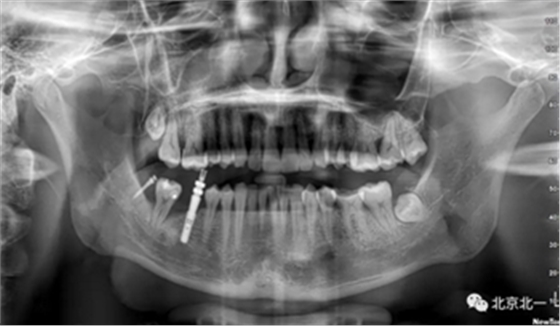

患者、男、40岁,下颌牙缺失数年来院咨询种植。

检查:46缺失, 47倾斜, 1度松动, 未见48萌出,

CBCT:骨量高度及宽度可, 48埋伏,低位阻生.37近中骨吸收

诊断:下颌牙列缺损, 48低位埋伏阻生 37 牙周炎

治疗计划:46种植, 同期拔除48 正畸扶正47.

术后拍片。

正畸支抗直立47

第一次支抗钉脱落, 第二次支抗钉位于48位置, 颊侧舌侧舌侧扣牵引。

直立后维持位置, 并取模戴牙。